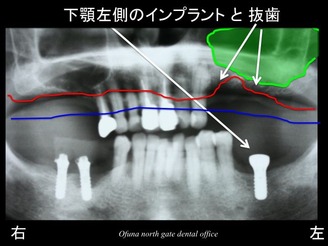

ここでいつものように 骨吸収の状態を線で書いてみましょう!

青線が骨吸収を起こす前の骨の位置です。

赤線は、現在の骨の位置です。

赤線まで骨が吸収したということです。

それでは、これも先程と同じように

骨吸収の状態を線で書いてみましょう!

骨吸収が非常に進行しているのが分かると思います。

実際に上顎洞を線で書いてみましょう!

先程解説しましたように この緑線の内側は骨ではありません。

さらに見やすくするために 上顎洞を緑色で塗りつぶしてみましょう!

現状では 骨吸収と 上顎洞の存在のため、インプラントを埋め込むことはできません。

骨の高さがほとんどないのです。